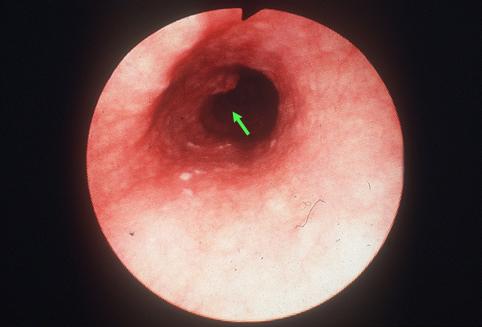

疾病(病理主体)的分类恶性上皮肿瘤/扁平上皮癌

部位(按器官分)食道/中

检查方法内窥镜

肿瘤的肉眼分类0型(表在型)/I型(Isp)

肿瘤最大直径15~19

肿瘤的深度sm